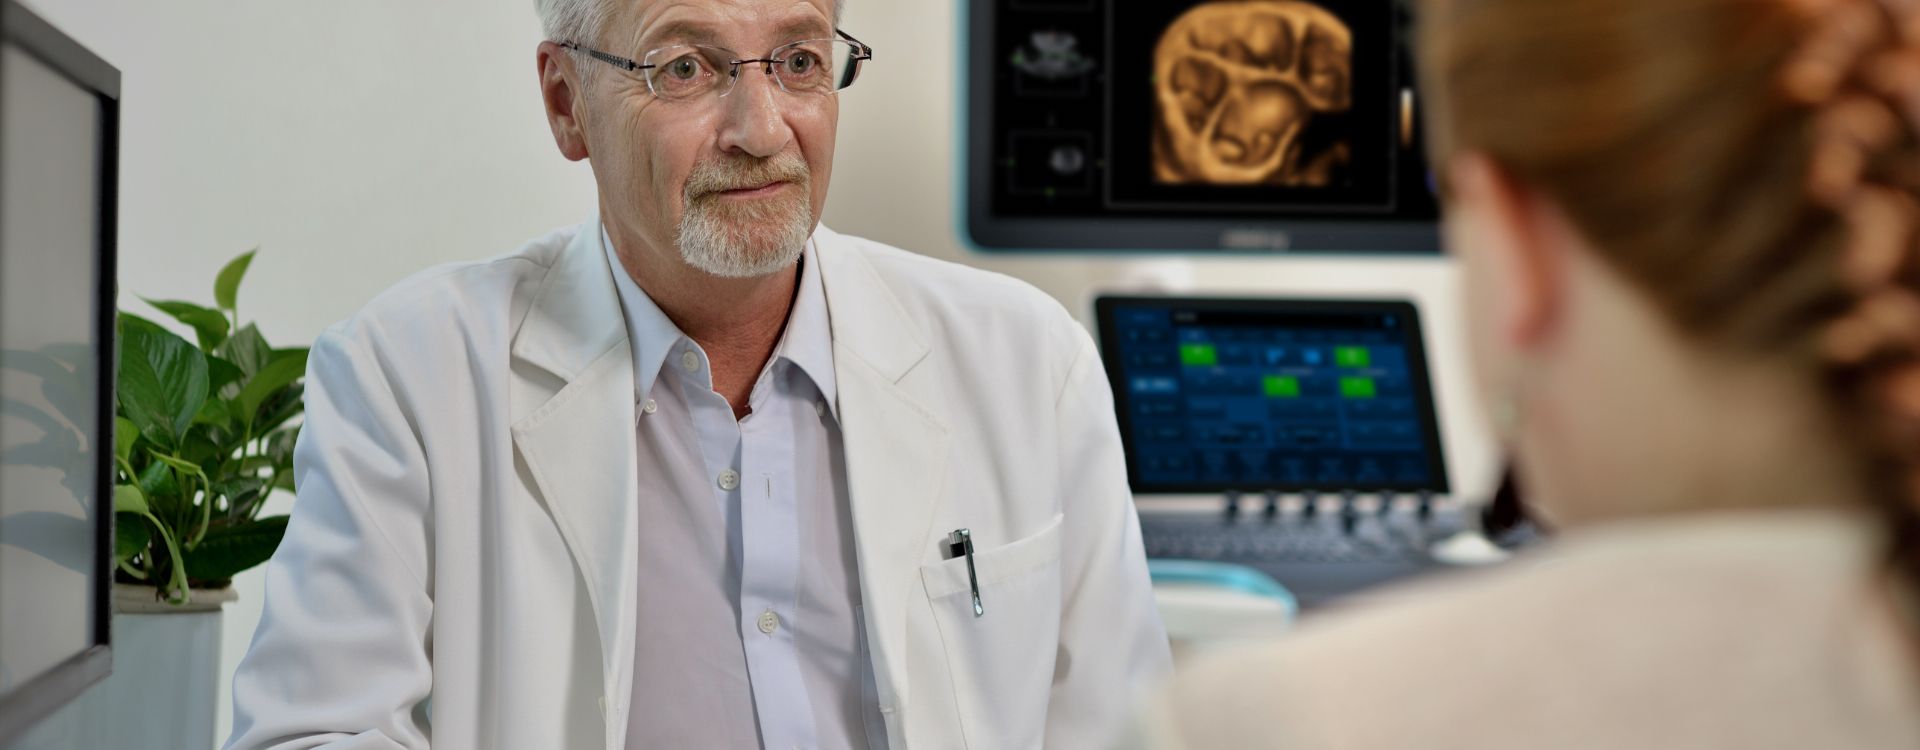

Precisie geeft vertrouwen

Algemene beeldvorming

Mindray Resona-oplossingen voor algemene beeldvorming helpen clinici bij het realiseren van nauwkeurigere en effici?ntere diagnose- en behandelingsresultaten door middel van sondes voor aparte toepassingen en effici?nte klinische toepassingstools.

De medische omgeving van vandaag is complexer geworden, met een toenemend aantal moeilijke gevallen en meer werkdruk.